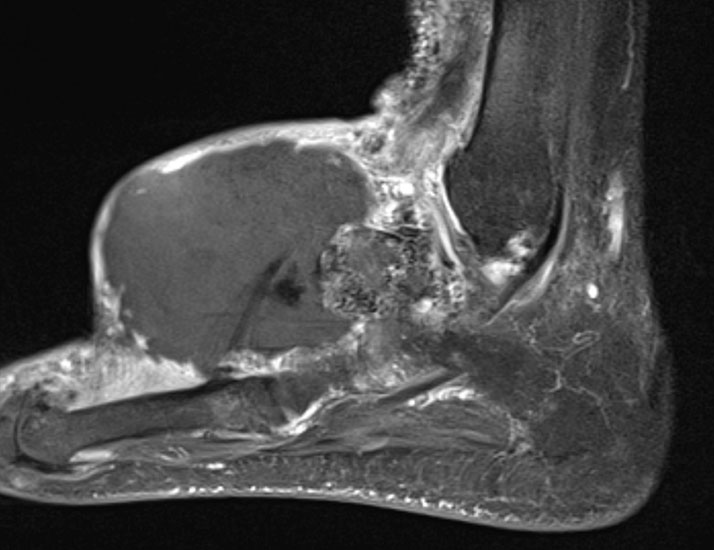

Synovialsarkom

MR-tomographische Darstellung eines unspezifischen weichteiligen Raumforderug im Bereich des dorso-lateralen Rückfußes. Die offene Probebiopsie ergab schließlich die Diagnose eines hochmalignen Synovialsarkoms.

Abbildung 34

10% aller Patienten mit Weichteilsarkomen weisen bei Erst­diagnose bereits Metastasen auf, meist in der Lunge. Drei Viertel der Weichteilsarkome zeigen eine schlechte histo­logische Differenzierung („high-grade“, G3 und G4) und die Letalität beträgt insgesamt über 30%. Trotz des vergleichs­weise seltenen Vorkommens (<1% aller Malignome) gilt diesen Entitäten aufgrund der schlechten Prognose erhöhte Aufmerksamkeit. Das Synovialsarkom ist der häufigste maligne Weichteiltumor im Bereich des Fußes und betrifft hier typischerweise Adoleszente und Erwachsene in der 2. bis zur 5.Lebensdekade (Abb. 34). Zwischen Beginn der Symptome und endgültiger Diagnose­stellung vergehen durchschnittlich 21 Monate. Das Synyovialsarkom zeigt einen unspezifischen klinischen Verlauf mit variabler Wachstumsge- schwindigkeit und kann zahlreiche andere Entitäten imitieren 50. Die Gefahr sowohl pulmonaler/hämatogener als auch lymphogener Metastasen ist hoch.